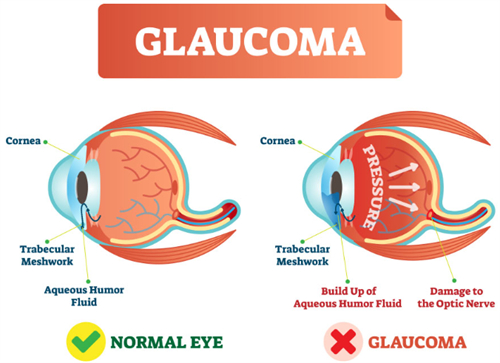

小梁切除术:针对开角型青光眼,通过改良缝合技术减少术后低眼压风险,单眼手术时长缩短至25分钟。

复合式小梁切除:结合抗代谢药物应用,手术可行性提升,尤其适合年轻患者。

青光眼白内障联合手术:一次手术解决两种眼病,减少患者反复麻醉风险,术后视力修复周期缩短。

小创口青光眼手术(MIGS):通过微小切口植入iStent引流管,创伤小,适合早期青光眼患者。

选择性激光小梁成形术(SLT):没有创口治疗早期青光眼,可重复操作,避免药物副作用。